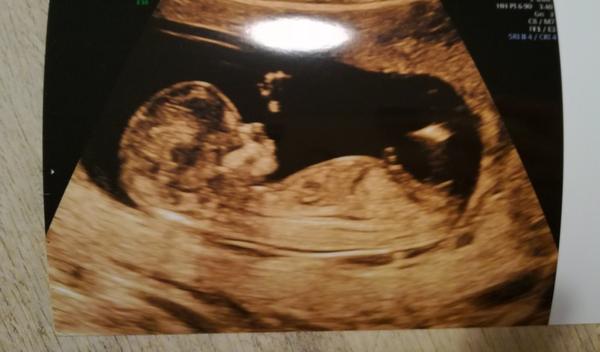

@mikejla_a ta tenká čárka v pravo dole by měl být pohl. hrbolek co směřuje nahoru 🙂

@mrnousek121 no me prave prijde,ze jde celkem rovnobezne s pateri...tak uvidime 😊

@fiendish.angel pokud je to za nožičkou pohlaví hrbolek tak by to měla týt holčička

@kristyna14092013 holčička. pohlavní hrbolek je souběžně s osou páteře. kdydy výrazně čněl nahoru, je to kluk 🙂